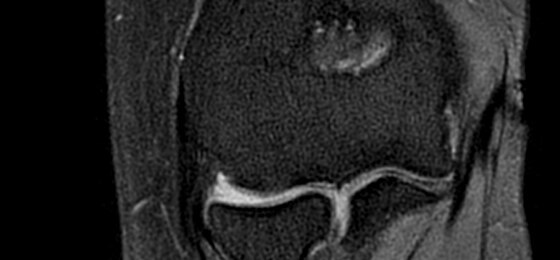

Make no substitutes for image quality

Clearly consistent images

Simply better compared to conventional coil technology.